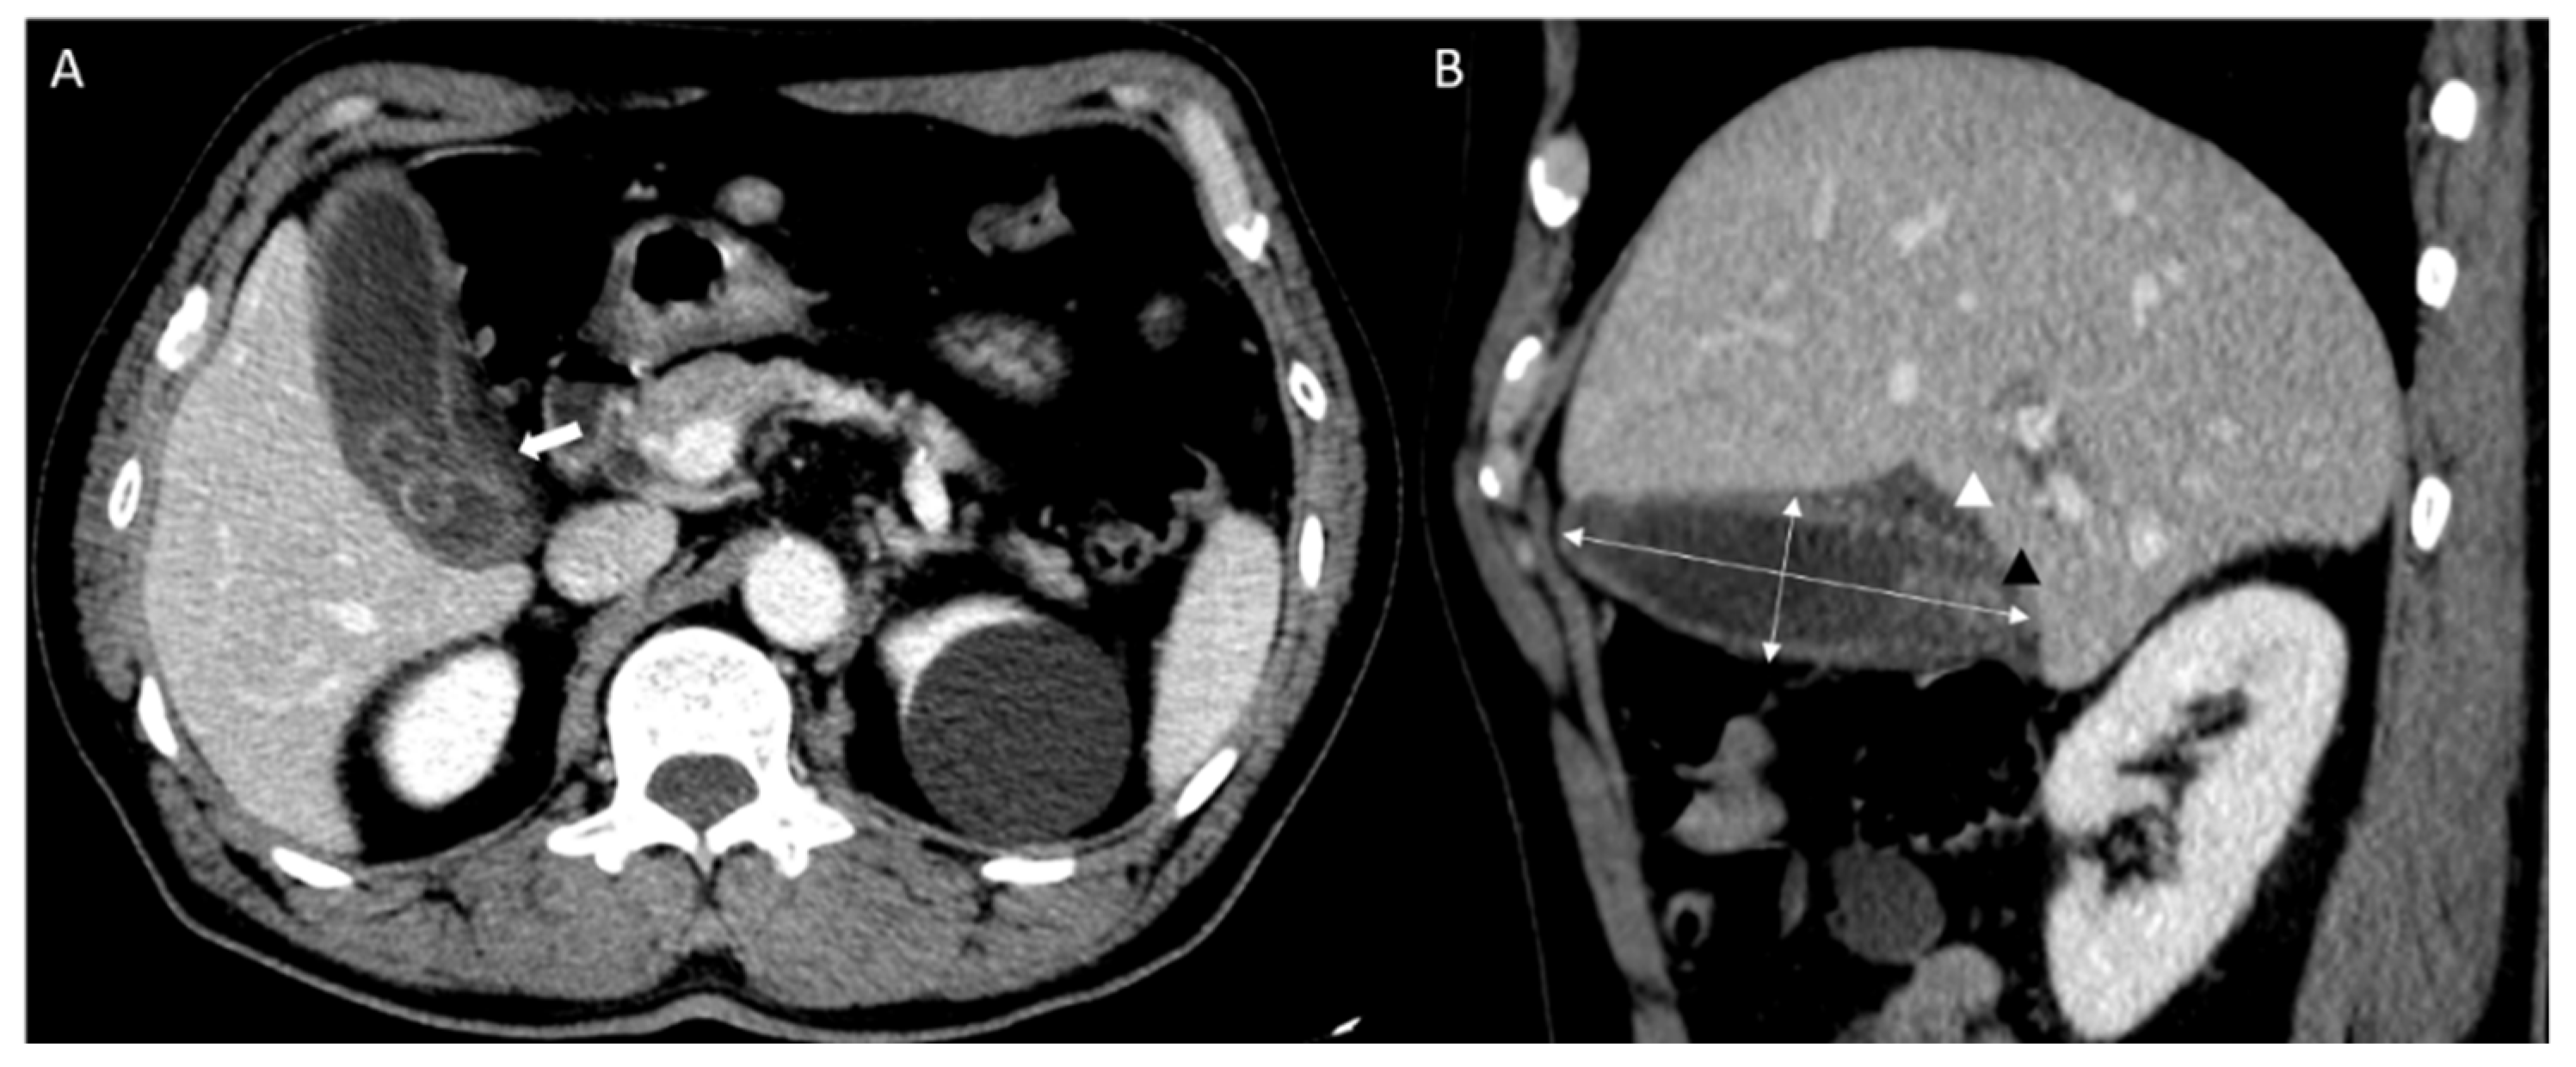

All CT scans were performed using a commercially available multidetector CT scanner (Discovery CT750 HD; GE Medical Systems, Milwaukee, WI, USA). CT images were retrospectively reviewed by two emergency physicians (P.Y.S. and Y.H.) from the records read by the radiologist. CT images of the cholecystitis and control groups were used to measure (1) gallbladder width, (2) gallbladder length, (3) presence of stones, (4) wall thickness, (5) pericholecystic fluid, and (6) fat infiltration. Gallbladder length was calculated using the maximum length among the axial, coronal, and sagittal planes of the abdominal CT, and the gallbladder width was measured using the greatest length of the outer-to-outer margin of the plane perpendicular to gallbladder length (Figure 2) [16].

Figure 2.

Abdominal computed tomography (CT) findings of acute cholecystitis in a 71-year-old with leukocytosis and right upper quadrant pain ((A) axial scan, (B) sagittal scan). Abdominal CT results showing gallbladder (GB) distension (double arrow; GB width, 3.36 cm and GB length, 9.34 cm) with impacted GB stone (black triangle). It demonstrates fat infiltration (white arrow) and pericholecystic fluid collection (white triangle).